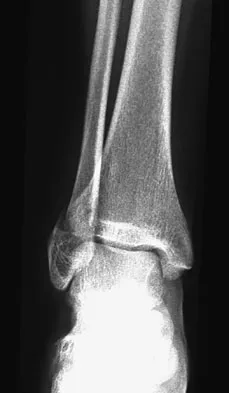

Figures 4a through 4c show the radiographs of a 43-year-old woman who sustained a twisting injury to her right ankle. She has ankle pain and tenderness medially and laterally. To help determine the optimal treatment, an external rotation stress radiograph of the ankle is obtained. This test is designed to evaluate the integrity of what structure?

Explanation

In the presence of a supination external rotation-type fracture of the distal fibula (Weber type B), stability of the ankle is best assessed by performing an external rotation stress AP view of the ankle. This test is used to assess the integrity of the deltoid ligament. The presence of a deltoid ligament rupture results in instability and generally is best managed surgically. The gravity stress test can also be used. Egol KA, Amirtharajah M, Tejwani NC, et al: Ankle stress test for predicting the need for surgical fixation of isolated fibular fractures. J Bone Joint Surg Am 2004;86:2393-2398. McConnell T, Creevy W, Tornetta P III: Stress examination of supination external rotation-type fibular fractures. J Bone Joint Surg Am 2004;86:2171-2178.